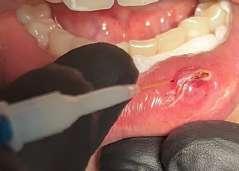

Il mucocele del cavo orale è la seconda lesione più comune. Nella fascia di età compresa tra 10 e 29 anni, il tasso di incidenza è più elevato. Il mucocele è caratterizzato da un accumulo di mucine. Ha una forma a cupola. Di solito hanno un colore bluastro. Il

mucocele si trova più comunemente sul labbro inferiore, seguito dalla mucosa buccale e dal pavimento della bocca. L'incisione tradizionale con bisturi e/o l'escissione chirurgica, la marsupializzazione, la micromarsupializzazione, l'iniezione di corticosteroidi, l'agente sclerosante, la criochirurgia, l'elettrochirurgia e il laser sono tutte procedure validate per il trattamento del mucocele in letteratura.

I laser a diodi forniscono una guarigione delle ferite e un tasso di recupero più rapidi rispetto ai loro rivali. Grazie alle sue

qualità antibatteriche e antinfiammatorie, questa terapia laser ha l'ulteriore vantaggio di migliorare la guarigione delle ferite senza infezioni o edema.

Le procedure laser-assistite sui tessuti molli presentano i vantaggi di un minimo sanguinamento intraoperatorio, edema e dolore postoperatorio, oltre a tempi chirurgici, cicatrici e coagulazione minimi.

La dimensione di un sito chirurgico determina se vengono utilizzate o meno le suture. Le procedure che comportano un'escissione piccola o significativa dei tessuti molli, l'esposizione dell'impianto con o senza taglio osseo, possono essere eseguite in pazienti con problemi di sanguinamento.

Questo caso è coerente con precedenti segnalazioni di escissione del mucocele utilizzando un laser a diodi.

L'enorme quantità di tessuto rimosso e il livello di comfort del paziente supportano ulteriormente il fatto innovativo che può essere utilizzato anche per il mucocele di grandi dimensioni.

I mucoceli della mucosa orale sono malattie tumorali benigne delle ghiandole salivari minori della mucosa orale. Si verificano più comunemente nella mucosa labiale. Possono essere causate da una rottura dell'epitelio della ghiandola che secerne saliva nello spazio extraghiandolare e forma una pseudocisti (mucoceli da stravaso) oppure da un blocco del flusso salivare dovuto ad una proliferazione epiteliale del dotto escretore che forma una cisti salivare (cisti da ritenzione).